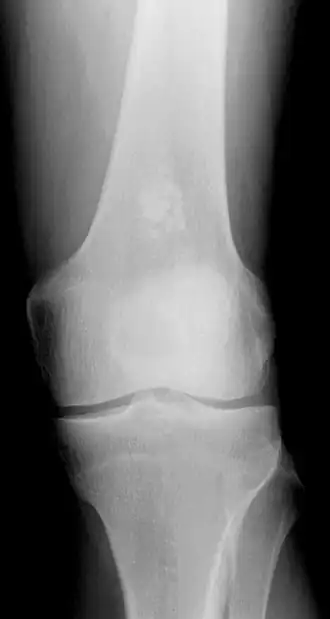

Encondroma do fêmur.

Em uma radiografia é visto como um osso aumentado, com maior radiotransparência, calcificações nodulares e menores que 3 cm. Fora das falanges fazem calcificações em anel ou em arco. Assemelha-se ao condrossarcoma de baixo grau devido à hipercelularidade, binucleação e alteração do mixoide, mas condromas são indolores e crescem muito mais lentamente. [4]